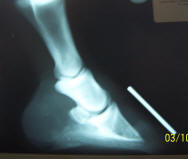

Aside

from the rotation, notice the calcification of the lateral cartilages

and osteophytes at the joints. |

6 months

later, the attending vet was quick to point out that the "derotation"

and the soundness of this horse were not nearly as important as the

speed at which the body is absorbing the calcifications. |

Immobile at start, pasture

sound in about one month; 6 months later, he's being comfortably ridden

daily on all terrain. It is very important to note how much larger the

"impact zone" behind P3 has become. Sound, heel-first impact is

developing the lateral cartilages.

I still hope for the coronet to migrate further

down P3 and am curious about whether the calcifications will continue to

disappear, so again, I'll post updated radiographs in 6 more months.